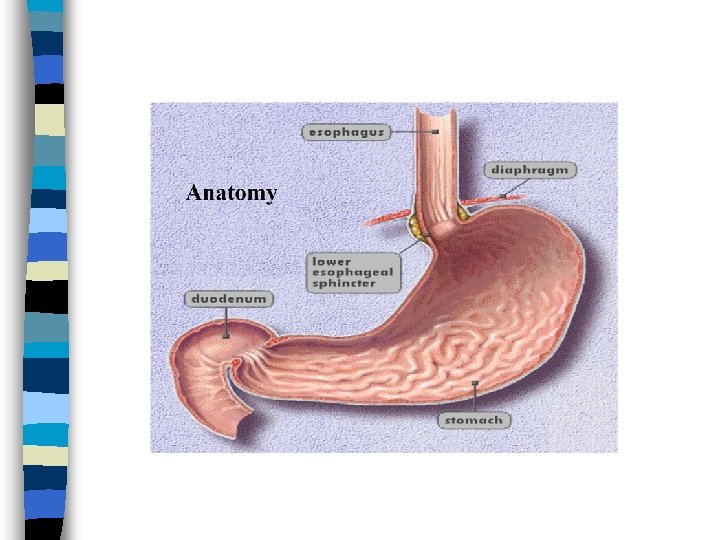

Factors contributing to LES Competence Angle of cardioesophageal junction n Action of diaphragm n Gravity n

GERD & Hiatal Hernia n Hiatal hernia occurs when the LES, upper part of the stomach moves up into the chest through a small opening in the diaphragm (diaphragmatic hiatus). n The diaphragmatic hiatus acts as an additional sphincter around the lower end of the esophagus